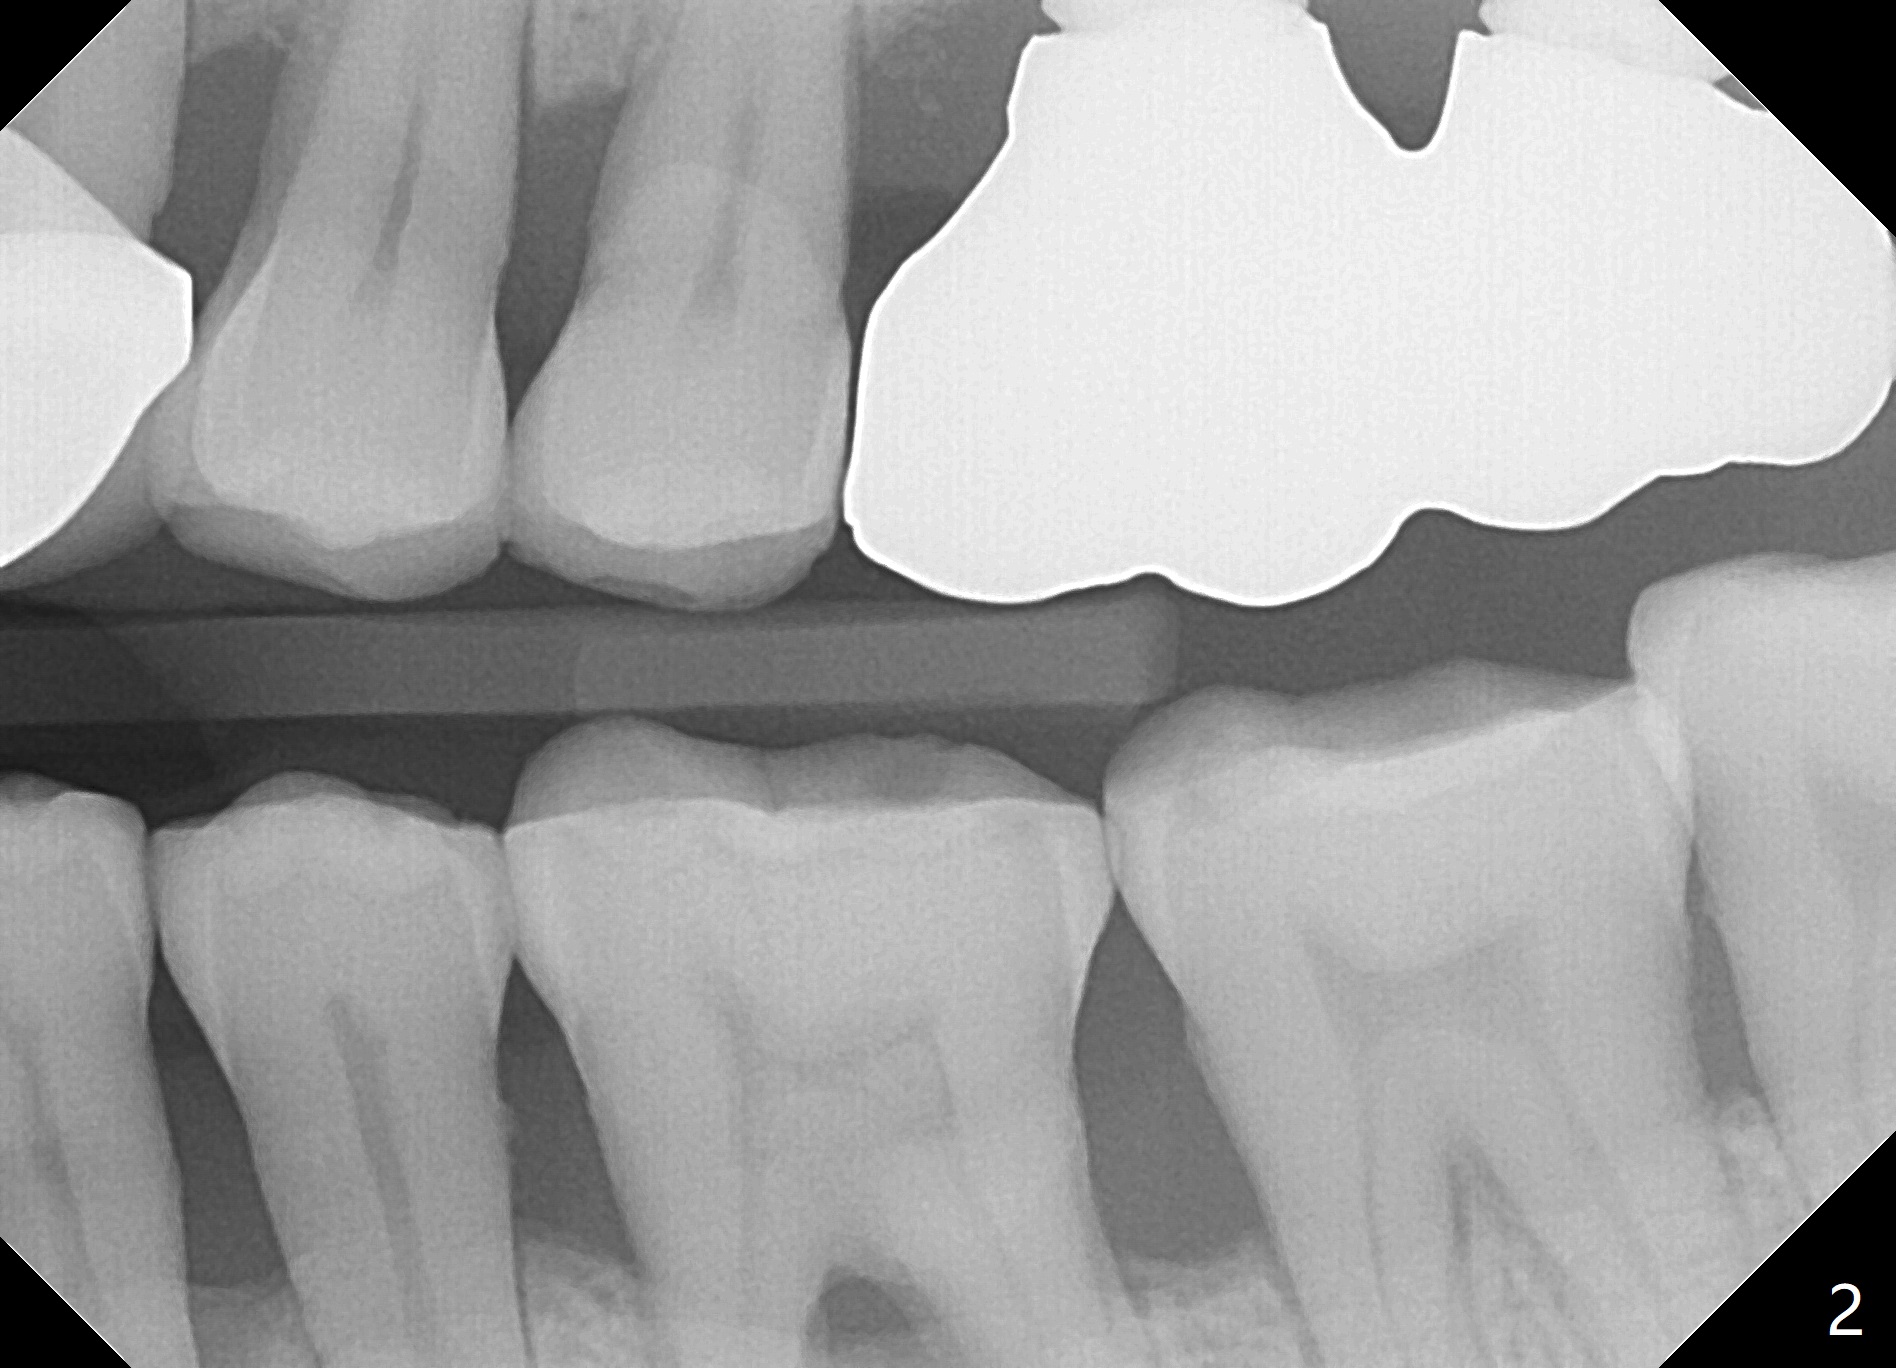

Improve Implant/Crown Ratio and Prevent Periimplantitis

A 59-year-old man seems to have perio-endo disease at #19 (Fig.1-3). To improve implant/crown ratio, place IS implant at the crestal level (not too deep). To prevent periimplantitis (buccal plate postop resorption), place the implant lingually. Prepare surgical handpiece to initiate osteotomy or to flatten the septum.